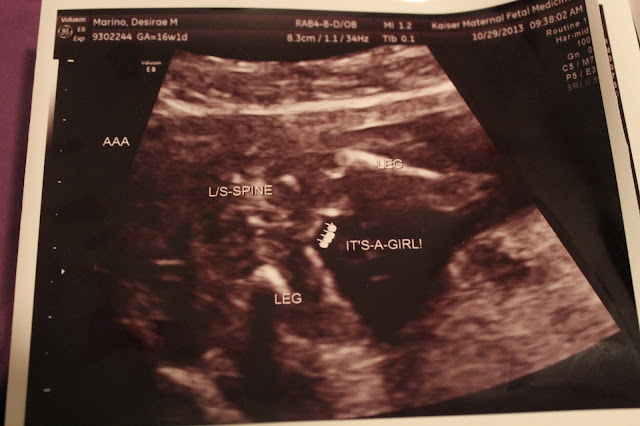

Here are some pictures of our beautiful babies:

| Baby A at 16 weeks |

| Baby B at 16 weeks |

Baby B's cute loser sign